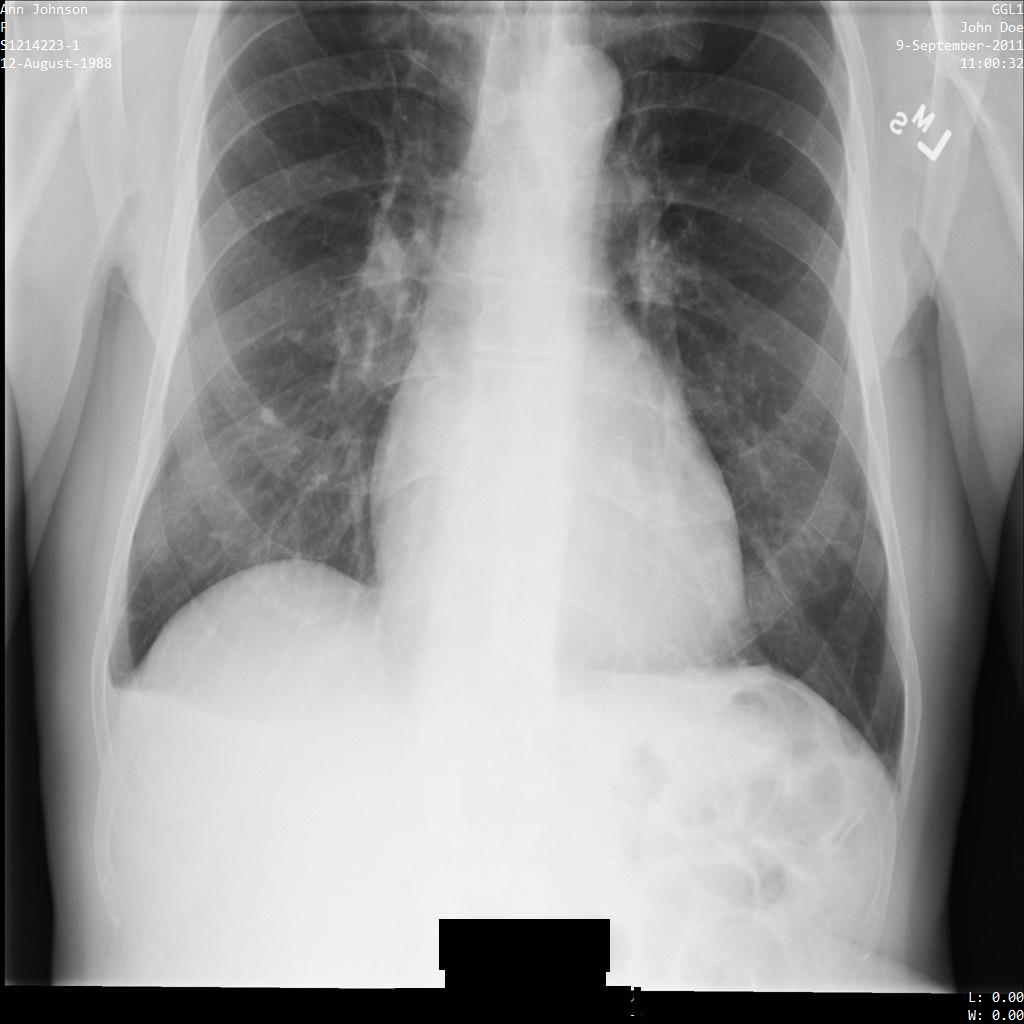

Ciascuna delle sezioni seguenti fornisce esempi di come anonimizzare i dati DICOM utilizzando vari metodi. Con ogni campione viene fornito un output dell'immagine deidentificata. Ogni campione utilizza la seguente immagine originale come input:

Puoi confrontare l'immagine di output di ogni operazione di deidentificazione con l'immagine originale per vedere gli effetti dell'operazione.

Dopo aver inviato l'immagine all'API Cloud Healthcare, l'immagine viene visualizzata come segue. Sebbene i metadati visualizzati negli angoli superiori dell'immagine siano stati oscurati, le informazioni sanitarie protette (PHI) incorporate nella parte inferiore dell'immagine rimangono. Per rimuovere anche il testo integrato, consulta Oscuramento del testo integrato nelle immagini.